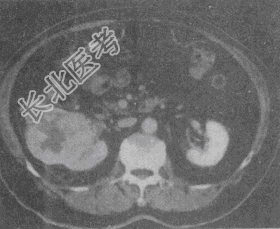

- 单项选择题患者,男, 51岁。右肾区不适4个月余,有镜下血尿。CT扫描结果见图。最有可能的诊断是

A、肾癌

B、肾盂癌

C、肾错构瘤

D、肾结核

E、肾腺瘤